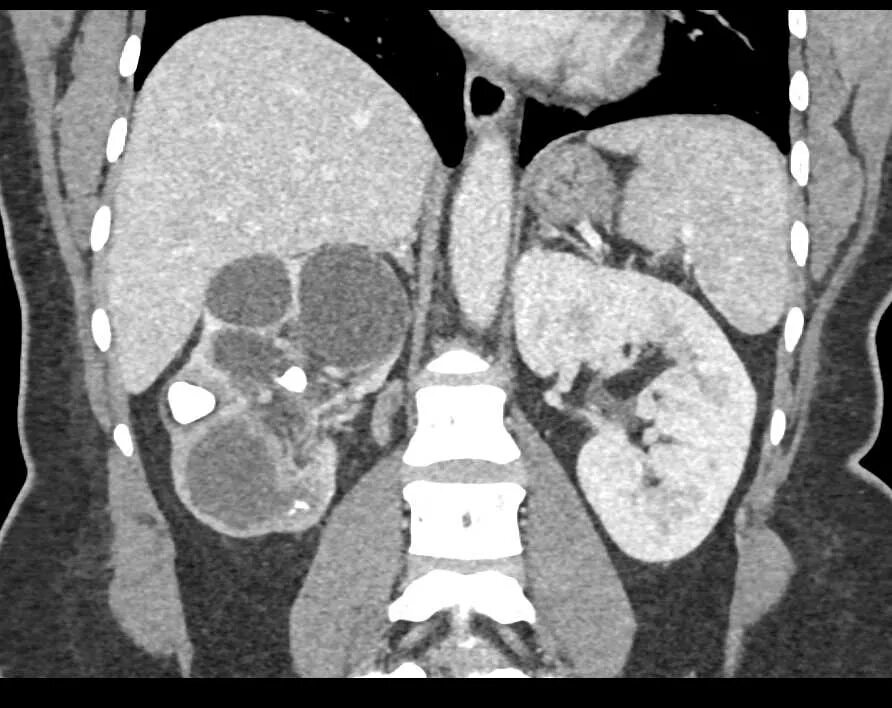

Пиелонефрит кт